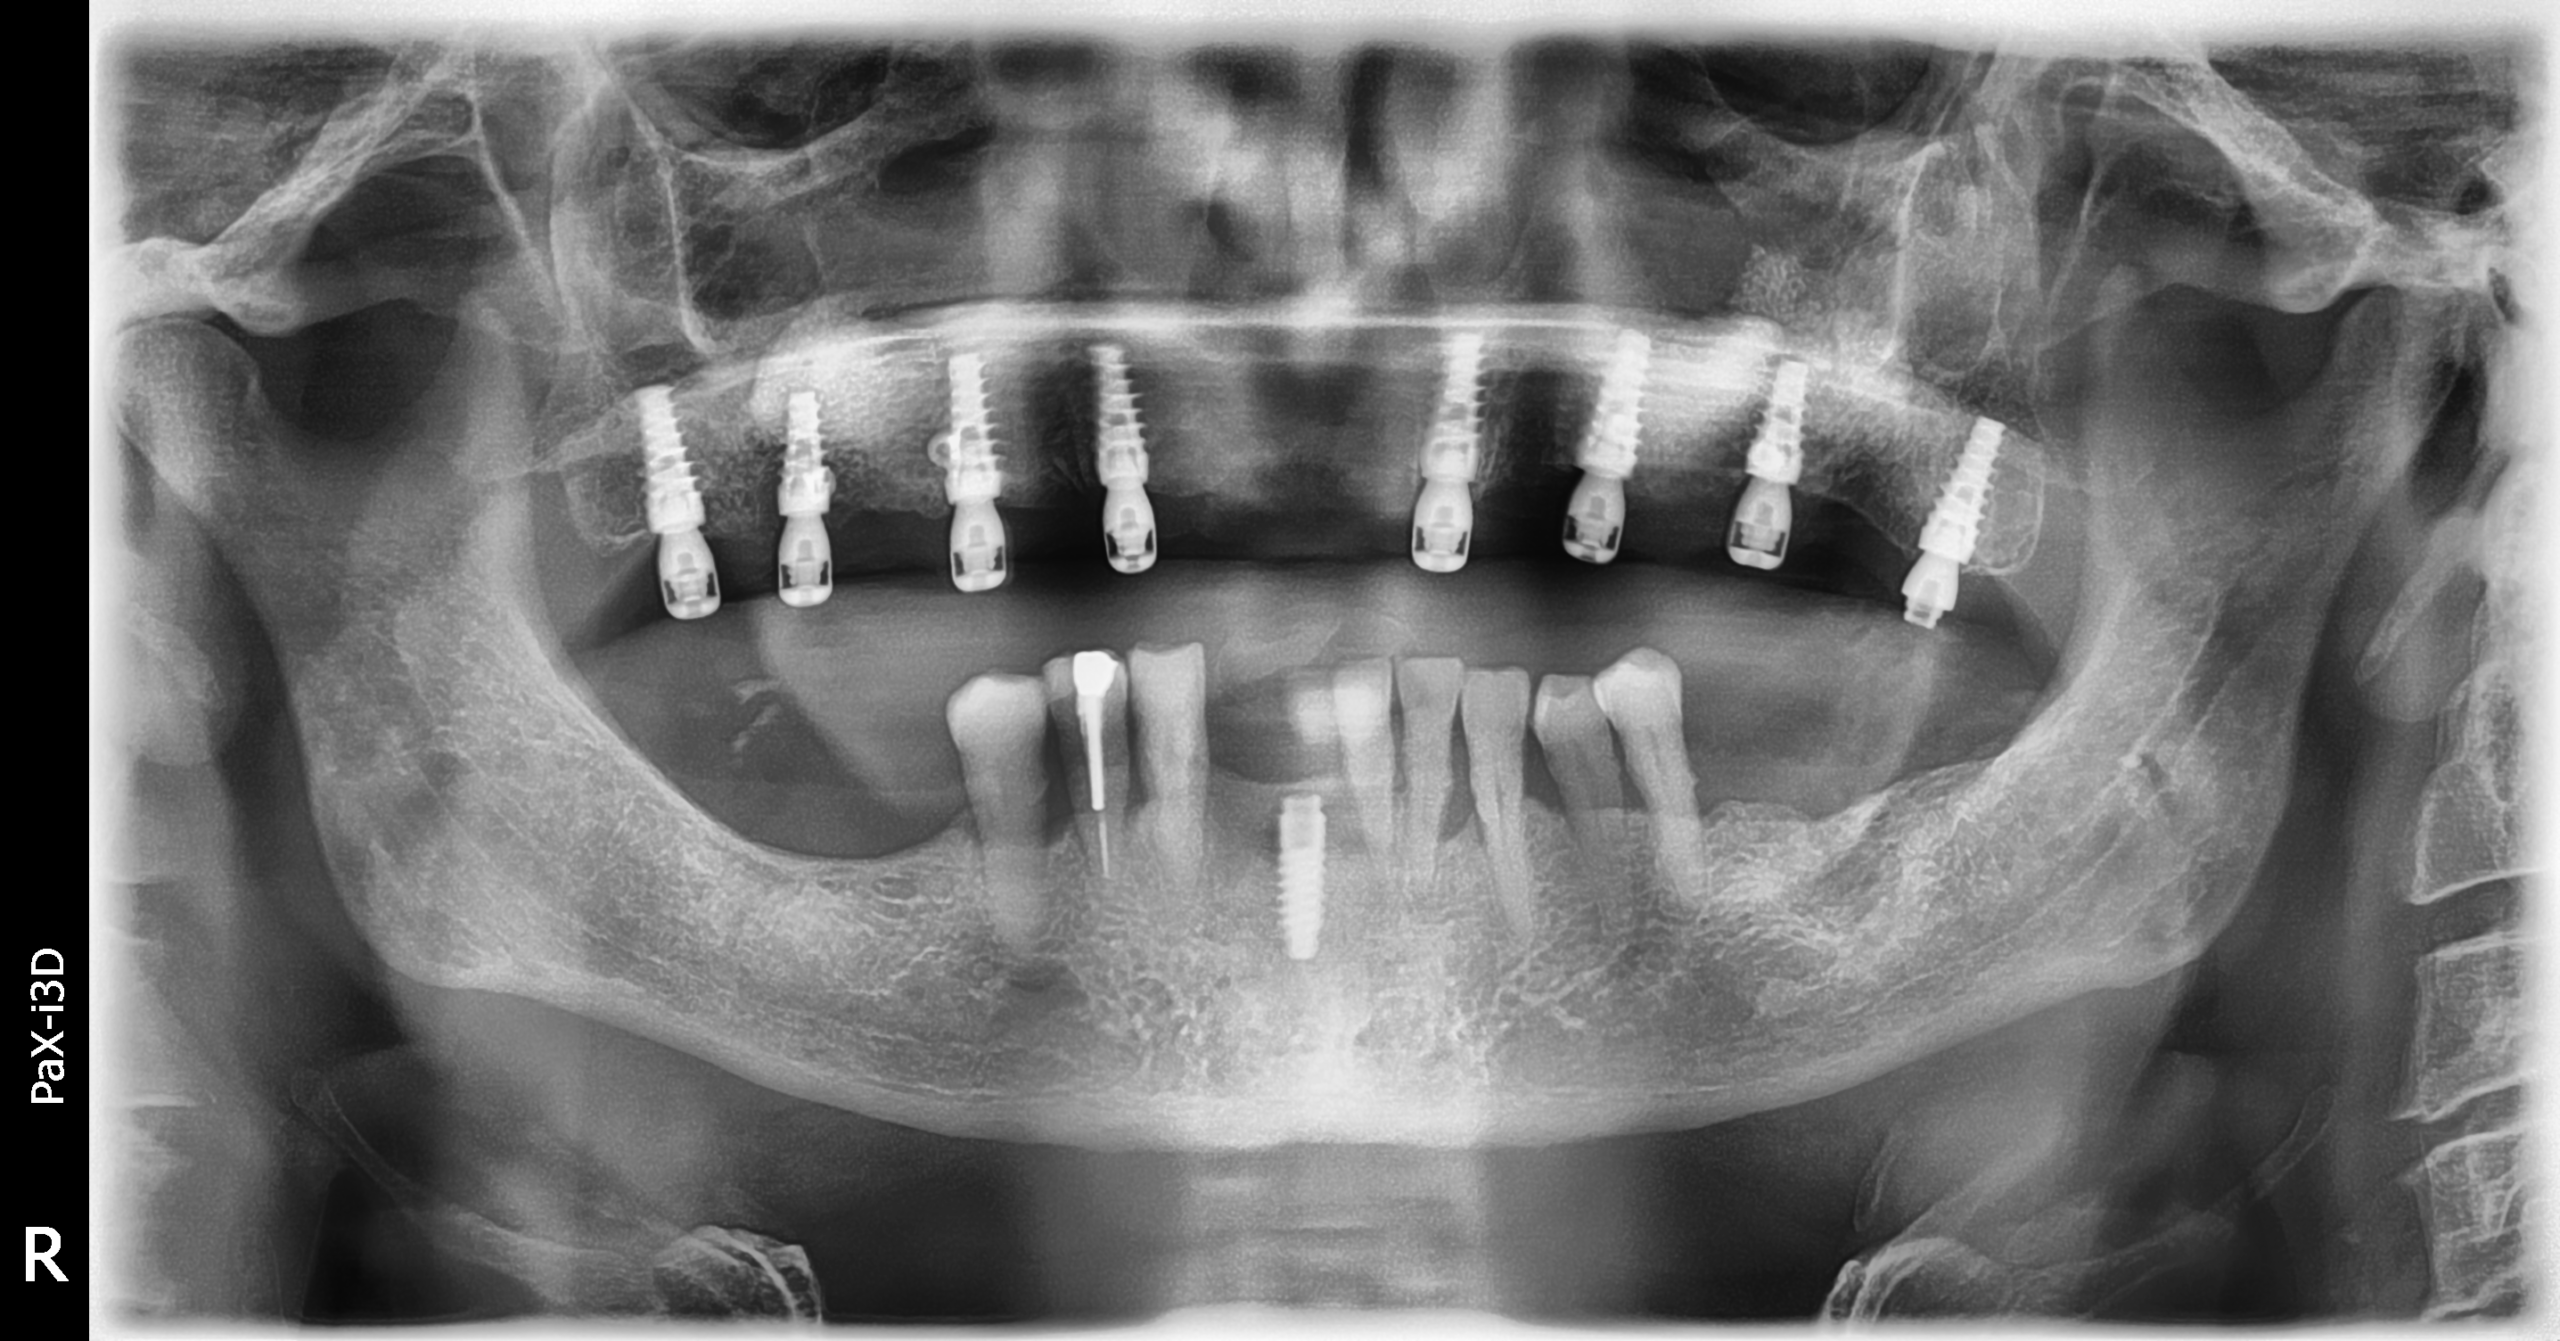

Implantes PCI

Secuencia de imágenes RX, antes y después de la inserción de implantes PCI en la parte superior e inferior de la boca.

Paciente varón de 75 años.

- Radiografía previa a la colocación de implantes Radhex.

- Colocación de implantes Radhex PCI en la parte superior